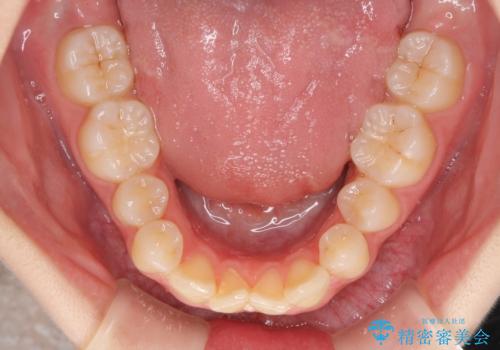

本人は気づいていませんでしたが、下顎前歯が2本欠損しており、上下の歯列がアンバランスとなりデコボコになっていました。

抜歯矯正を行ったことで、デコボコが改善されただけでなく、口元も下がったことで口が閉じやすくなりました。